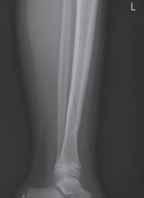

Rycina 17.82.

Uszkodzenie tętnicy podkolanowej wskutek złuszczenia nasady bliższej kości piszczelowej (S-H 1). Zagrożenie rozwojem zespołu przedziałów powięziowych jest poważne.

Rozpoznanie

Objawy złamania to silny ból uniemożliwiający stanie i chodzenie, zniekształcenie obrysów stawu kolanowego przez krwiak i różnego stopnia przemieszczenie nasady kości piszczelowej. Należy dokładnie zbadać stan ukrwienia i unaczynienia kończyny pod kątem objawów uszkodzenia tętnicy podkolanowej i nerwu strzałkowego. Trzeba ocenić bolesność uciskową oraz napięcie w przedziałach powięziowych podudzia: przednim, bocznym, tylnym powierzchownym i tylnym głębokim. U pacjentów z podejrzeniem wzmożonego ciśnienia wewnątrzprzedziałowego należy wielokrotnie powtarzać badanie ukrwienia i unerwienia kończyny, a w razie zaistnienia wskazań wykonać bezpośredni pomiar ciśnienia w przedziałach. Powinno się zawsze podejrzewać możliwość uszkodzeń więzadłowych współistniejących ze złamaniem. Badania obrazowe to RTG w pozycji AP, bocznej i skośnej. Wykonanie badania TK może być konieczne w celu pełnej oceny rozległości

złamania. W przypadku podejrzenia uszkodzenia tętnicy podkolanowej należy wykonać angio-TK lub arteriografię.

Leczenie

Leczenie złamania bliższej nasady piszczeli w przypadku uszkodzenia typu 1 i 2 według Saltera i Harrisa leczymy nieoperacyjnie. Należy wykonać zamkniętą repozycję i unieruchomić w opatrunku gipsowym udowym w zgięciu kolana 30–60°, zapewniającym najlepszą stabilność odłamów. Okres unieruchomienia wynosi od 6 do 7 tygodni. Po tym czasie usuwamy gips i zaczynamy ćwiczenia zwiększające zakres ruchomości stawu kolanowego oraz wzmacniające siłę mięśnia czworogłowego. Ważne jest, by prowadzić częste kontrole stanu ukrwienia i unaczynienia oraz kontrole radiologiczne w celu wykrycia ewentualnych przemieszczeń odłamów. Złamania pierwotnie niestabilne lub wtórnie przemieszczone wymagają zamkniętej repozycji stabilizacji drutami K. Typ 3 i 4

Złamania rzepki i podudzia

złamania według Saltera i Harrisa wymaga leczenia operacyjnego w postaci otwartej repozycji i stabilizacji śrubami. Należy unikać krzyżowania metalu zespalającego z chrząstką wzrostową. Kończynę zgiętą w kolanie do 30° unieruchamia się w gipsie udowym na okres 6–8 tygodni. Po tym czasie rozpoczynamy ćwiczenia czynne poprawiające zakres ruchomości kończyny.

Powikłania

Zespół ciasnoty przedziałów powięziowych

Zespół ciasnoty przedziałów powięziowych może wystąpić wskutek uszkodzenia tętnicy podkolanowej (10% przypadków). Wynika on ze ścisłego powiązania tętnicy z torbą stawową na wysokości proksymalnej części piszczeli. Należy ściśle monitorować stan kończyny i unikać okrężnych opatrunków gipsowych.